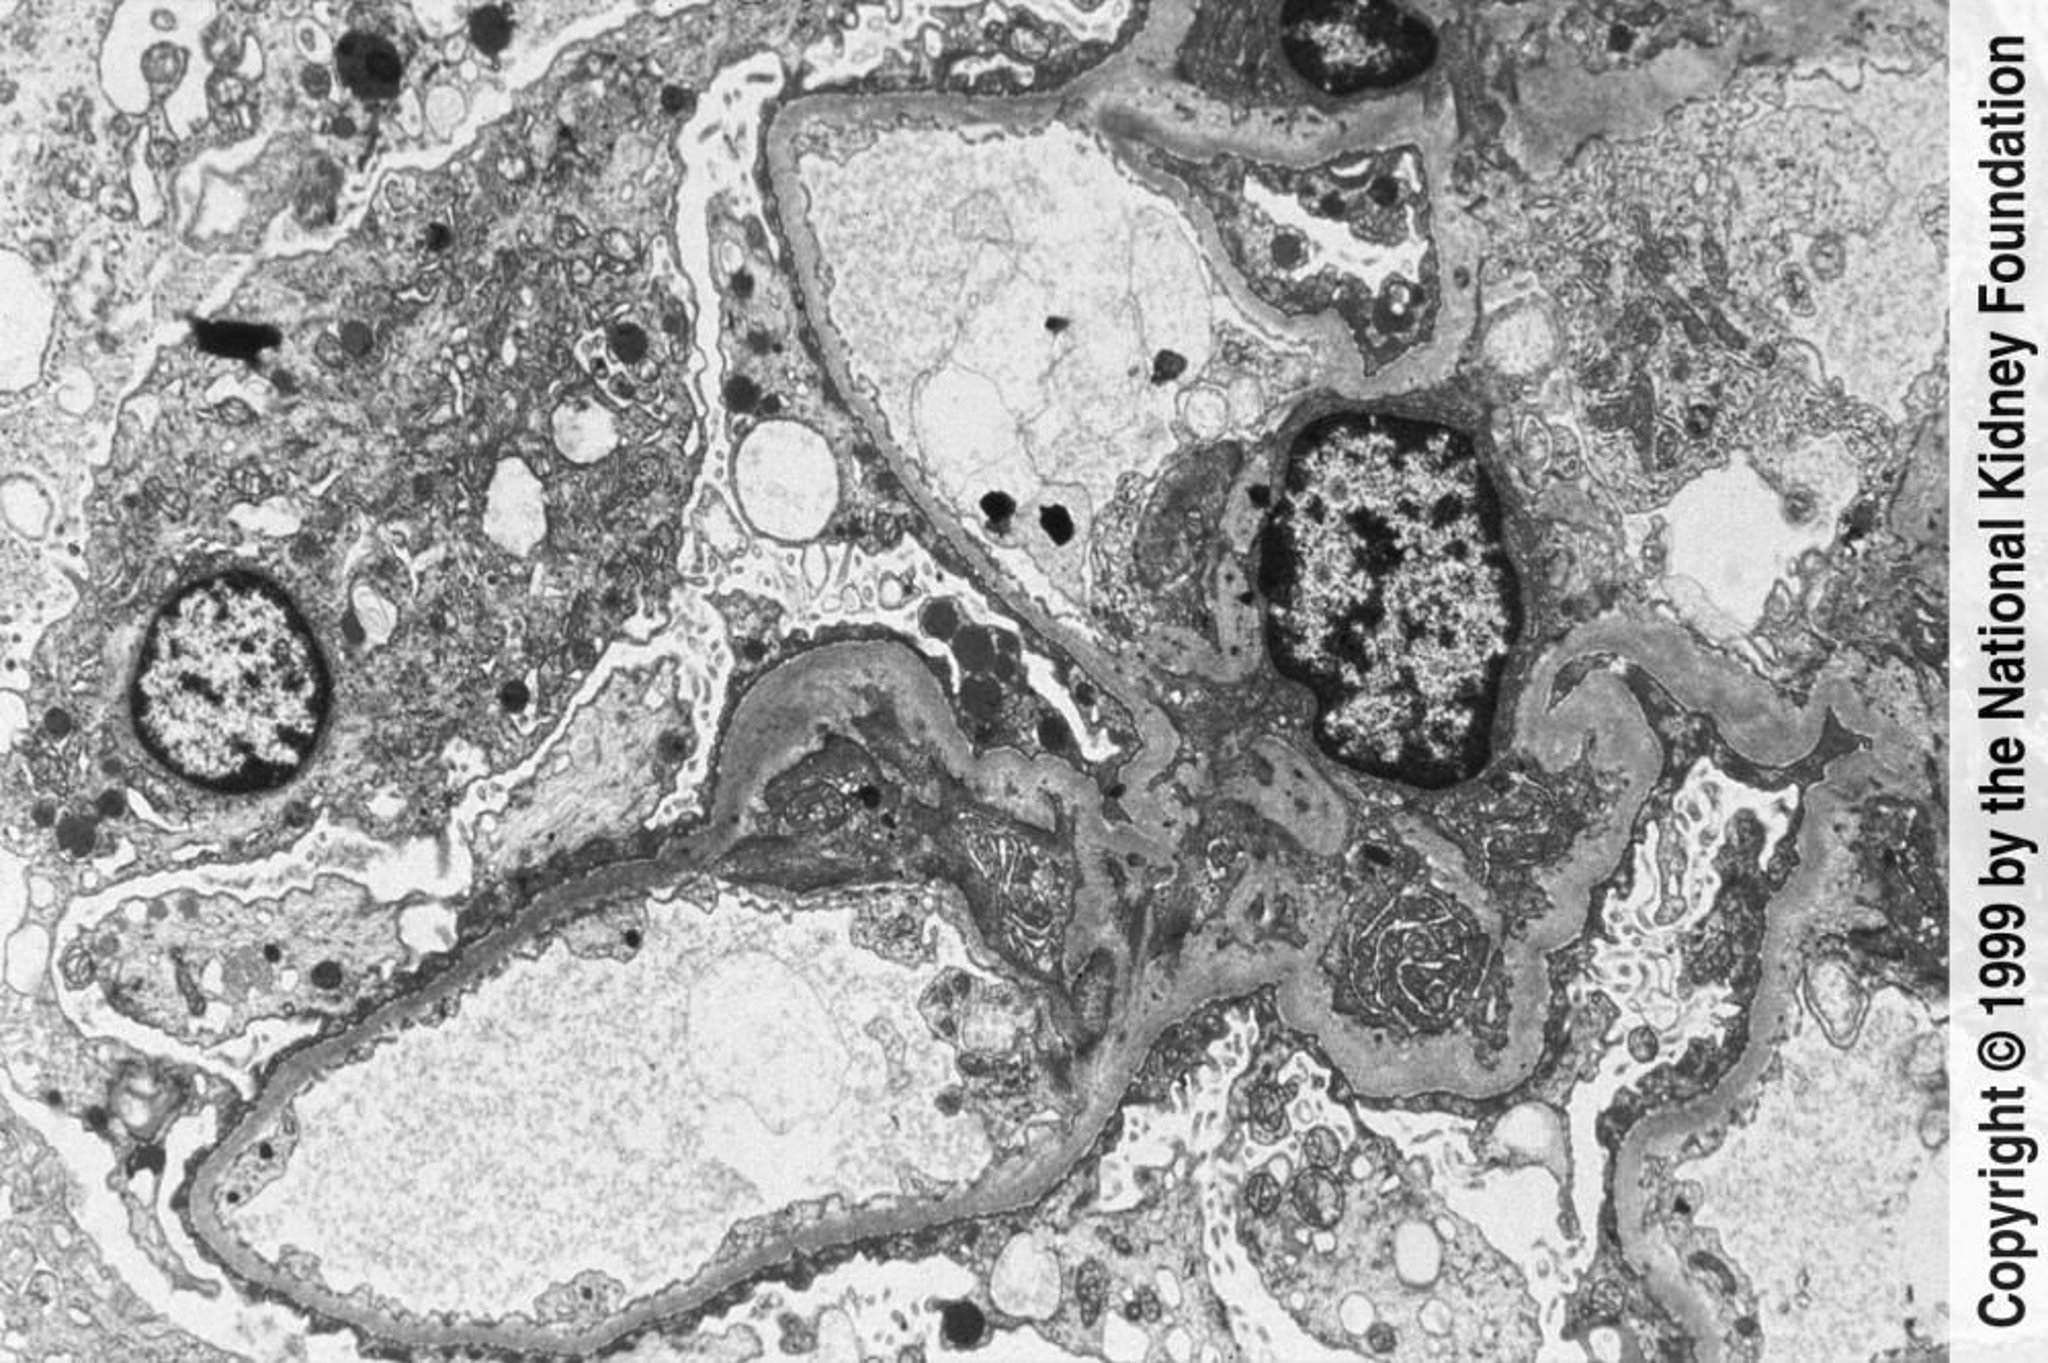

Glomérulosclérose segmentaire et focale (émoussement et effacement des pédicelles)

La microscopie électronique à transmission étendue permet d'observer un important décollement et l'effacement des pédicelles (×3000).

Image fournie par Agnes Fogo, MD, and the American Journal of Kidney Diseases' Atlas of Renal Pathology (voir www.ajkd.org).